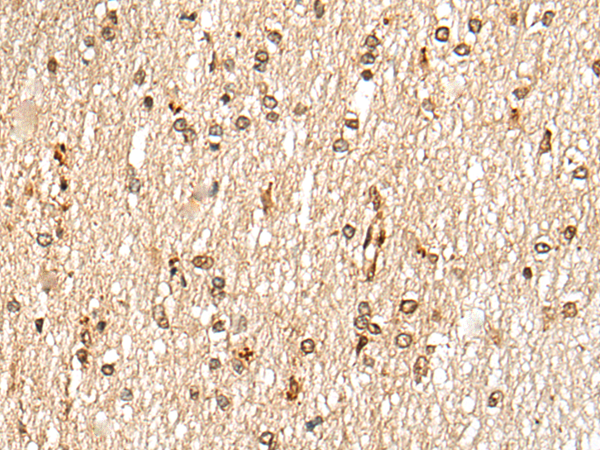

IHC positive control: |

Human thyroid cancer and human esophagus cancer |

IHC Recommend dilution: |

20-100 |